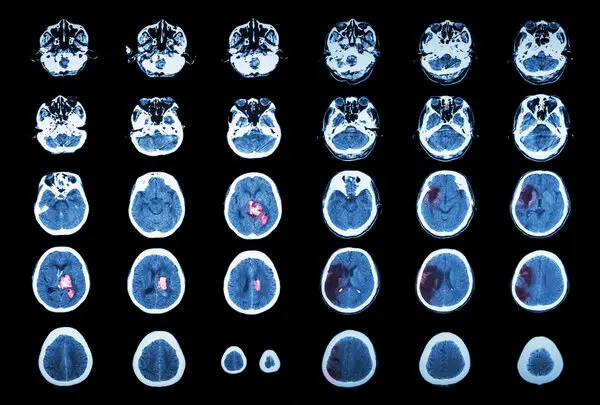

They work for depression and PTSD. Could they also help the brain repair itself after a neurologic catastrophe?

In the 15 years that Dr. Sean Dukelow has been treating stroke patients at Foothills Hospital in Calgary, Canada, he has had just one proven tool to offer them: neurorehabilitation. Performing the same actions over and over in speech therapy, physical therapy and occupational therapy has been shown to harness the brain’s natural plasticity, leading to neuron growth and new connections. “There’s going to be a lot of repetition,” he warns his patients.

Beyond that, therapies to boost long-term recovery are scant and limited to invasive implants that stimulate the vagus nerve or spinal cord. Now, neurologists are racing to find the first substance or device that could grease the wheels of healing — a turbo boost for brain recovery. “That turbo boost may be the difference between you walking again, talking again, being able to get home, versus having to go to a nursing home,” Dr. Dukelow said.

Promising contenders include transcranial magnetic stimulation, antidepressant pills and psychedelics, therapies that are better known for treating conditions like depression, post-traumatic stress disorder and obsessive-compulsive disorder. In psychiatry, these methods are thought to hack into the circuits that underlie memory and learning — the same circuits posited to animate stroke recovery.

The hope is that, in addition to changing old thought patterns, such therapies can help the brain find different ways to do the things it used to do — letting us walk, speak, remember — by forging new paths around dead and damaged neurons. But can therapies used to reset a disordered brain also help to repair a damaged one? Here’s what scientists know.